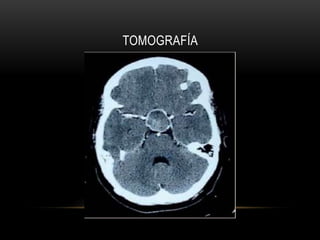

TOMOGRAFÍA